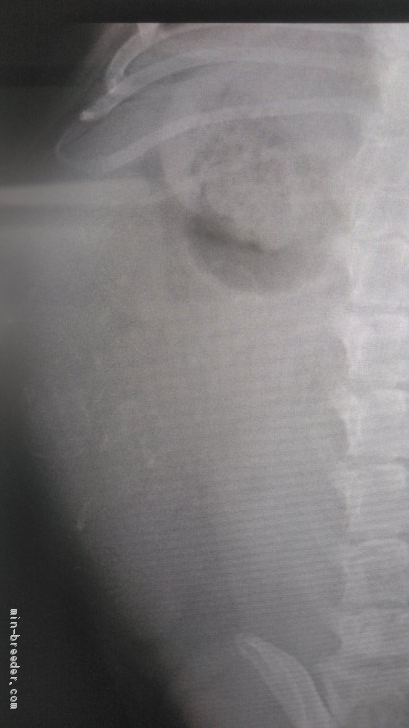

出産予定日まで4日🤭何頭かなぁ〜?出産予定日まで4日‼︎ てんちゃんレントゲン🩻撮影しました❣️ 5頭かなぁ〜? ...